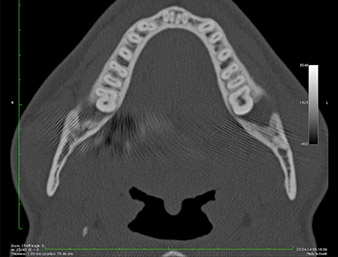

Nell'immagine 3D (tomografia volumetrica digitale) era visibile che il residuo di radice era collocato in posizione distocaudale nella transizione dalla porzione orizzontale alla porzione ascendente della mandibola (Fig. 2).

Immagine DVT

Fig. 2: Immagine DVT trasversale del residuo di radice nella regione retromolare.